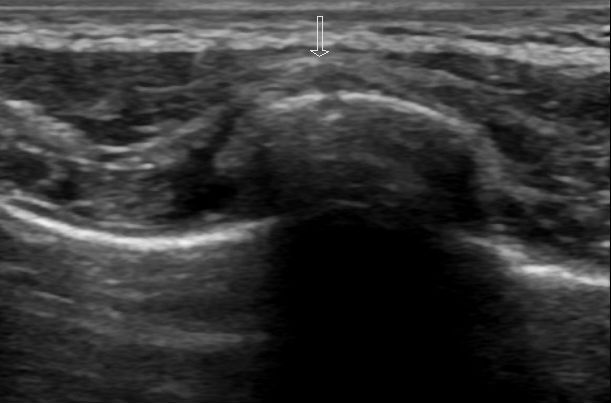

Figure 4:

Transverse view again demonstrating a cortical break with overlying hematoma.

Using a linear probe, place it perpendicular to the rib obtaining a transverse view and tracing the length of the rib at the site of highest tenderness. Observe for cortical disruption and surrounding hematoma as this can suggest a rib fracture. A longitudinal view should also be obtained for confirmation of findings.